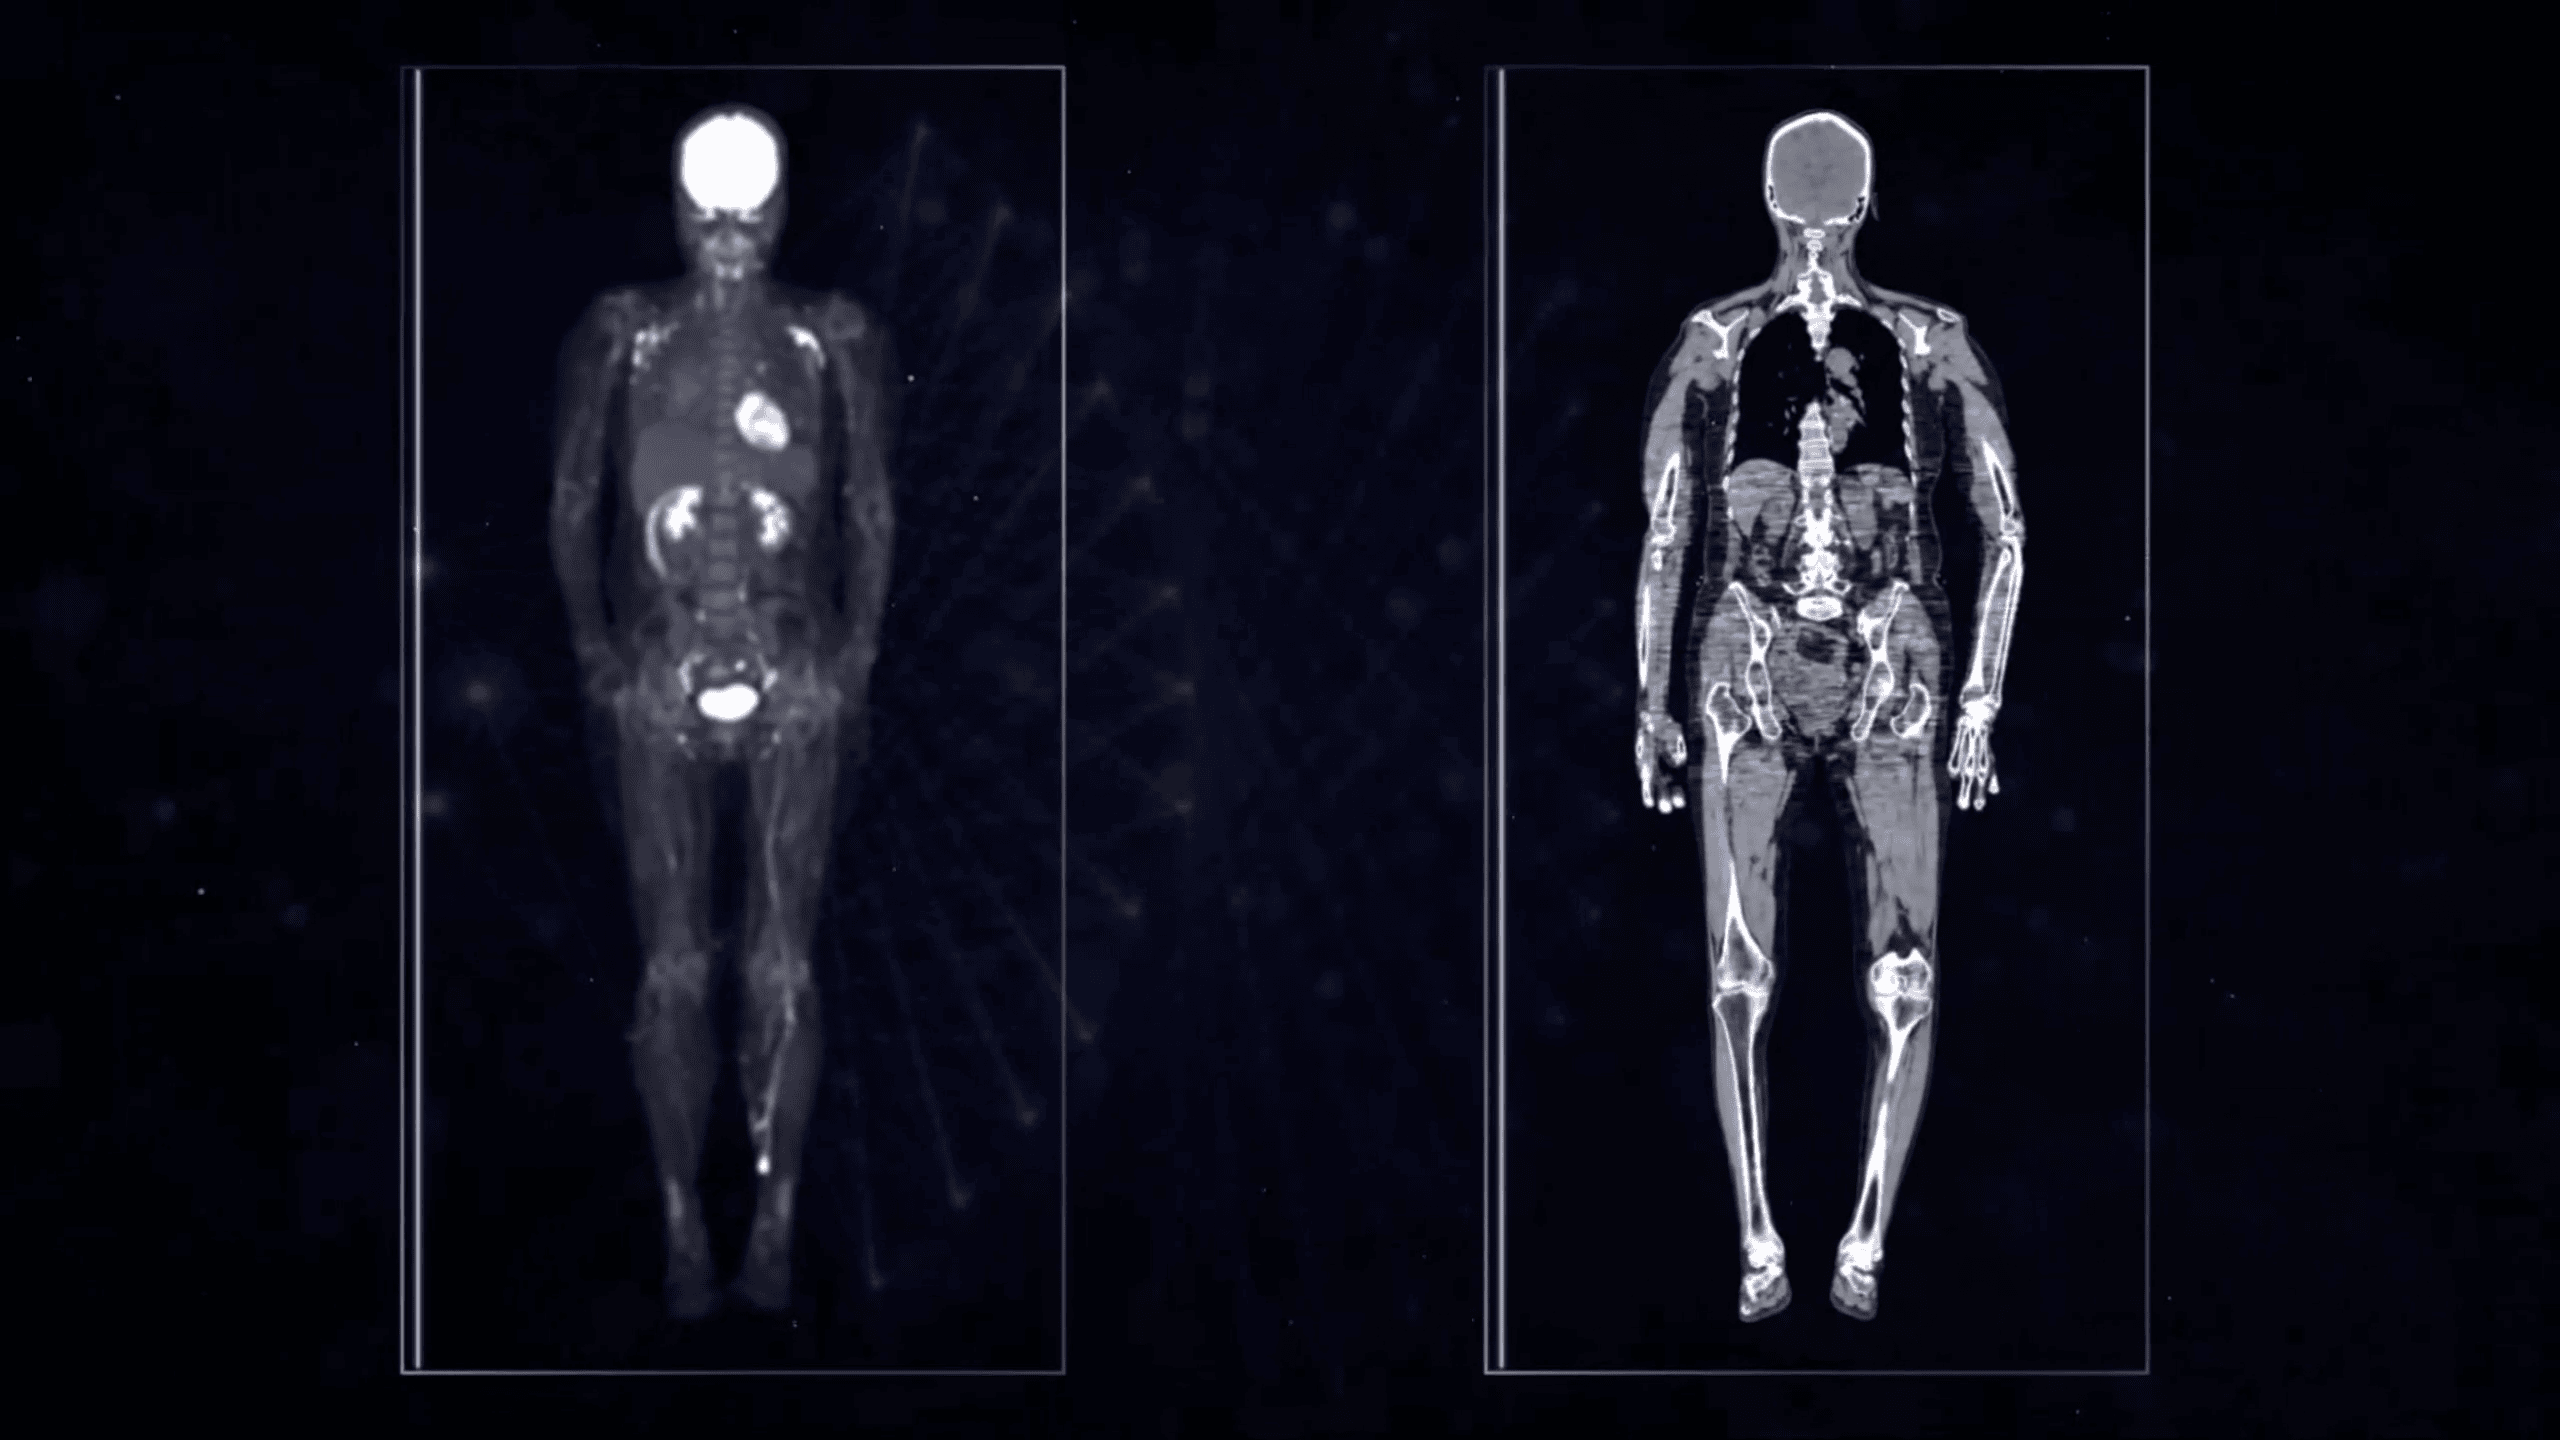

194 cm Axial FOV pentru acoperire total-body

uEXPLORER dispune de un câmp axial de vizualizare de 194 cm, cu 564.480 elemente cristaline, design modular și asamblare fără spații. Această arhitectură inovatoare oferă acoperire completă a corpului, reduce erorile sistemice și asigură imagini PET/CT cu rezoluție spațială ridicată și fuziune precisă.

Sensibilitate de 40x mai mare cu FOV axial de 194 cm

Cu un câmp axial de vizualizare de 194 cm, uEXPLORER captează mult mai mulți fotoni γ, depășind cu 30–40 de ori sensibilitatea sistemelor PET/CT convenționale. Tehnologia inovatoare de cross coincidence permite achiziția semnalului între unități adiacente, oferind o sensibilitate ultra-înaltă și uniformă pe întreg corpul, inclusiv la nivelul organelor vitale.

Detector digital cu ghid de lumină integrat

uEXPLORER utilizează tehnologia SiPM, care crește eficiența conversiei fotoelectrice și reduce pierderile de semnal, oferind o calitate superioară a imaginilor PET/CT. Cristalele microscopice ultra-fine îmbunătățesc semnificativ rezoluția, asigurând detalii clare și diagnostic de precizie.